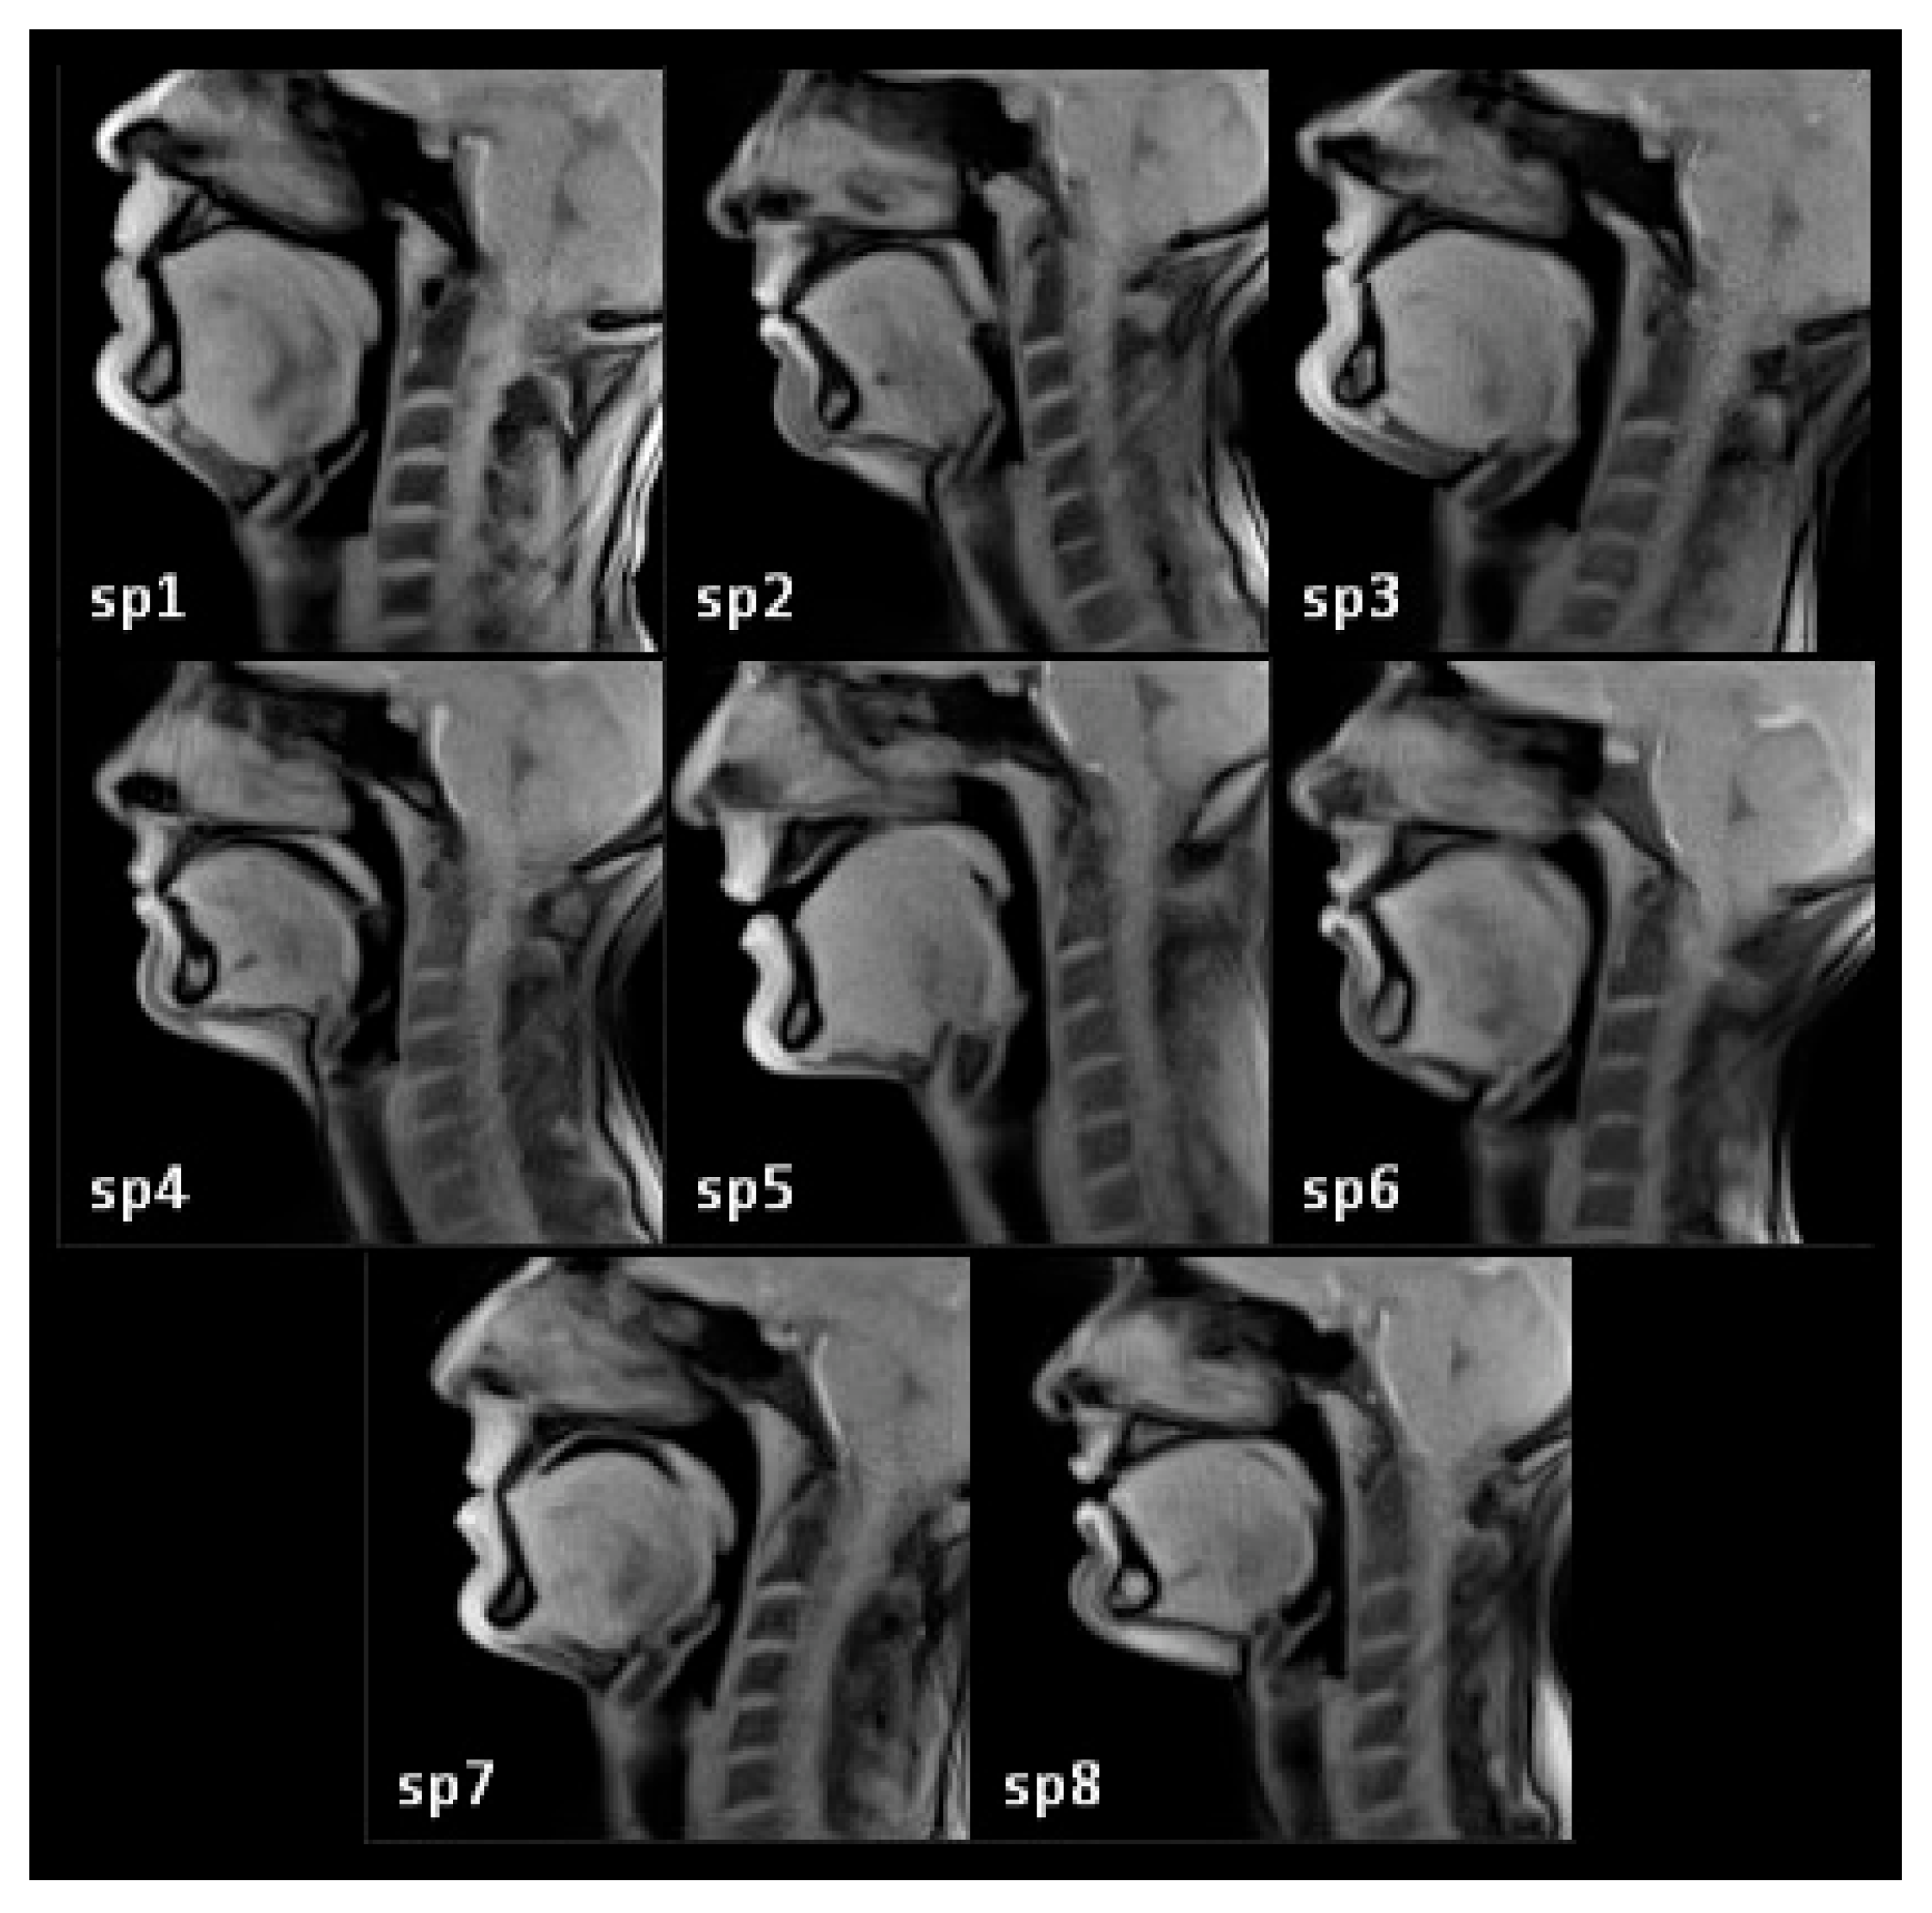

2.1. Subjects

| Speaker | Length (mm) | Height (mm) | Width (mm) |

|---|---|---|---|

| SP1 | 97 | 92 | 40 |

| SP2 | 77 | 76 | 32 |

| SP3 | 99 | 81 | 40 |

| SP4 | 89 | 69 | 34 |

| SP5 | 94 | 86 | 36 |

| SP6 | 87 | 81 | 32 |

| SP7 | 88 | 90 | 38 |

| SP8 | 87 | 67 | 34 |

| Mean | 89.8 | 80.3 | 35.8 |

| SD | 6.5 | 8.6 | 3.1 |